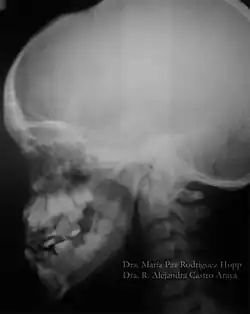

O diagnóstico do portador de DCC é realizado através de exames clínicos e radiográficos. A aparência clínica dos acometidos é bastante característica, principalmente após a puberdade devido a alguns traços dessa doença, como baixa estatura, falha na erupção dos dentes permanentes, dentes supranumerários e retardo na esfoliação dos dentes decíduos. Outros aspectos dessa patologia são: a aplasia ou hipoplasia clavicular (clavículas rudimentares ou completamente ausentes), que está presente em 10% dos casos, que permite o movimento do braço até ao plano sagital mediano. A abóboda craniana aumentada, uma menor espessura do músculo masseter, hipodesenvolvimento do terço médio da face, geralmente também é apresentado uma hipoplasia da maxila, retardo no desenvolvimento esquelético, o pescoço largo e atraso no fechamento das suturas cranianas. Em alguns casos é possível observar que os palatos estreitos e profundos também são frequentes. É importante realizar o diagnóstico diferencial devido aos pacientes exibirem nanismo, ossos densos, frágeis e agenesias parciais das falanges dos dedos dos pés e mãos.[9][10]

O atraso na erupção dos dentes pode ser explicado pelo aumento na densidade óssea de algumas regiões dos maxilares, em decorrência de uma remodelação anormal do osso; ausência ou diminuição do cemento celular; aumento da espessura da fibromucosa; presença de dentes supranumerários; formação incompleta da lâmina dentária e ausência de rizólise dos dentes decíduos. Jensen e Kreiborg (1993a, 1993b) têm relatado anormalidades morfológicas na maxila e mandíbula destes pacientes. Na maxila, os seios paranasais podem estar pequenos ou ausentes. Na mandíbula, os ramos ascendentes apresentam-se paralelos entre si e os processos coronóides mostram uma curvatura para a distal, além da persistência da sínfise mandibular. Também na face, os ossos nasais são hipoplásicos ou ausentes e os zigomáticos, hipoplásicos.

No estudo realizado por McNamara et al. (1999) sobre as características da síndrome, encontradas nas radiografias panorâmicas, citam-se a presença de múltiplos dentes não irrompidos; dentes com alterações de forma; ramos ascendentes da mandíbula delgados com os bordos posterior e anterior paralelos e, em alguns casos, estreitando-se em direção ao processo coronóide e côndilo; processo coronóide frequentemente ascendente e para posterior; arco zigomático estreito com severa inclinação descendente e algumas vezes descontínuo com a sutura zigomático-temporal; seios maxilares pequenos ou ausentes; bordo infraorbital mais baixo que o normal em relação aos dentes; inclinação descendente do assoalho da fossa nasal em relação à espinha nasal anterior, acentuando a forma em V; trabeculado ósseo da mandíbula com aspecto grosseiro; aumento da densidade da crista óssea alveolar, comprometendo a irrupção dentária; aumento da densidade do ramo ascendente entre o bordo anterior da mandíbula e o canal dentário inferior. A maior parte dos pacientes com disostose cleidocraniana desempenha suas funções normais, não apresentando comprometimento significativo. Existem relatos de que o tratamento cirúrgico com a exposição dos dentes inclusos, combinado com o tratamento ortodôntico, tem sido bem-sucedido em alguns casos (McDONALD, 2001). Porém, a extração dos dentes decíduos não promove a erupção dos dentes permanentes inclusos.[11]

Sabe-se que a retenção prolongada dos dentes decíduos, agenesias e dentes supranumerários provocam má oclusão. Portanto, procedimentos ortodônticos devem ser utilizados com a finalidade de adequar a cavidade bucal para futura reabilitação protética. Os exames radiográficos, além de auxiliar na detecção das anormalidades maxilofaciais, permitem o acompanhamento dos pacientes, sendo, por isso, considerados uma ferramenta para o diagnóstico e conduta terapêutica.[11]